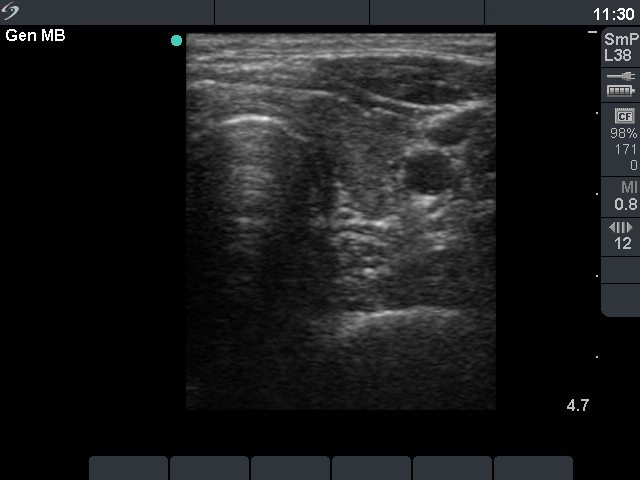

Ultrasonography: The thyroid was moderately hypoechogenic and showed increased vascularity. There was an echonormal nodule in the right lobe with combined perinodular and intranodular vascular pattern.